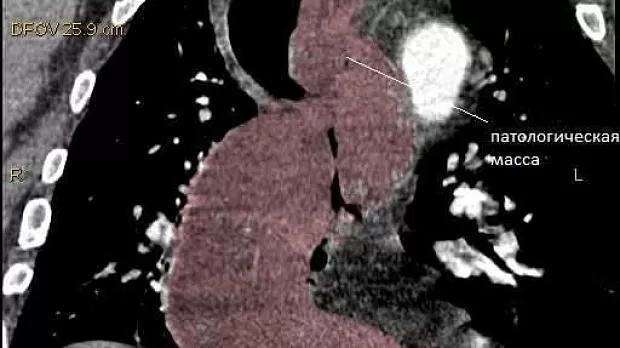

Дословного описания КТ под рукой сейчас нет основной смысл такой: патологическое образование в просвете пищевода длиной до 30 см и толщиной в своей самой толстой части до 6 см. Исходит похоже из задней стенки пищевода т.к. на большем протяжении остальной части образования можно проследить сепарацию от стенок пищевода. Пищевод сильно растянут. Образование солидное. литое. с некоторой неоднородностью. видны небольшие сосуды. Плотность может соответствовать лейомиоме. За пределы пищевода не выходит.